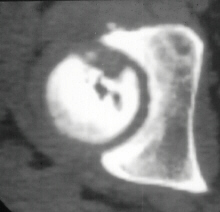

At 28 years of age, he had been having increasing pain in his right hip. He had a limp when he was tired. Positive Trendelenburg's sign was observed on the right. Internal rotation was limited to 25 degrees. All other motions were normal. X-ray showed cystic change. At the 29 years of age, he underwent bone graft of the right femoral head for degenerative cyst. At 35 years of age, only internal rotation was limited to 20 degrees. He still had pain in his hip that relates primarily to weather or to excessive walking. Only internal rotation was limited to 20 degrees. He had hip pain at the extremes of flexion and internal rotation. X-ray showed the progression of the cystic change. CT which was performed because of the question of loose bodies in the hip did not seem likely that the densities were actually in the hip joint. The antero-medial location of the cysts facing the anterior margin of the acetabulum was well depicted in CT.